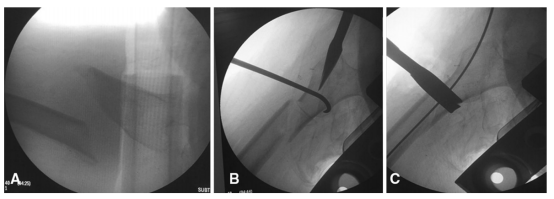

球钉推进器、骨钩或Hohmann拉钩等器械可用于直接复位骨折,方法是在骨折处作辅助切口,并钝化剥离骨折部位的筋膜。必须战略性地选择器械的位置,以便进行适当的节段处理(如图3a-c所示)。如果使用球钉,建议用2.7mm钻头在骨头上打一个小的单皮质孔,以避免器械滑动和移位。在典型的股骨粗隆下骨折中,远端骨折是内收的,用骨钩进行外侧牵引远端骨折块可能有助于复位。在这种特殊的情况下,需要一个大约3~4厘米的辅助切口,钩子应该从后面通过到远端骨折的内侧。然后,外科医生可以外展并抬高远端片段,以实现骨折充分复位和导丝的通过(如图4A,B所示)。类似地,可以用骨钩复位近端骨折,然后用复位骨夹固定(如图5a-c所示)。对于复杂粉碎性骨折,通过同一切口,可以用柯克氏钳操作骨折块(如图6A,b所示)。

图5 A移位的股骨粗隆下长斜形骨折;B使用骨钩进行复位;C用复位骨夹进行固定维持复位

图6 A\B使用柯克氏钳进行股骨粗隆下粉碎骨折辅助复位